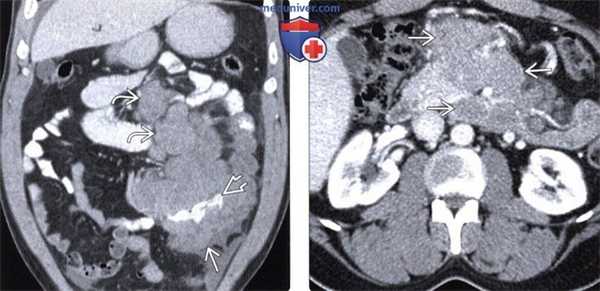

(Слева) При аксиальной КТ без контрастного усиления выявлена увеличенная селезенка с прилежащей к краю органа гиперденсной гематомой («сторожевой» сгусток) и свободная гиподенсная кровь в брюшной полости.

(Справа) Макропрепарат, полученный при операции у этого пациента, представляет собой поврежденную селезенку, увеличенную вследствие заболевания мононуклеозом. Длина этой селезенки около 20 см, при гистологическом исследовании выявлена массивная инфильтрация органа Т-лимфоцитами.